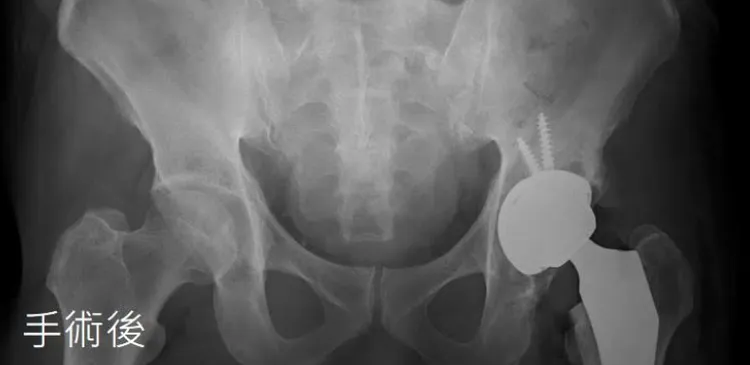

亞洲大學附屬醫院醫療副院長、骨科主治醫師黃揆洲指出,林男就醫時表示平時抽菸、喝酒,原本年輕時頂多只是偶爾悶痛,沒想到最近一年來症狀越來越嚴重,不僅爬山會痛、甚至連爬樓梯都苦不堪言,門診檢查時,髖部僅稍稍內旋與外轉,就讓他痛到大叫,醫療團隊建議置換人工髖關節,術後三天即出院,手術部位幾乎無傷口、一個月後就邀集好友繼續享受山林之樂。

林男經置換人工髖關節後3天即可出院。亞大醫院提供

黃揆洲指出,人工髖關節手術常見之併發症包括長短腳、髖關節偏移不正確造成術後疼痛,以及髖臼杯位置放置不佳手術後脫臼等狀況,透過新引進的3D列印技術「全髖植入物手術導引系統」,術前可動態模擬最佳化植入角度,3D列印導板則將骨盆前傾角設定為0度,減少骨盆前傾角差異,精準度媲美價格昂貴的機器人手術,費用則大幅降低。